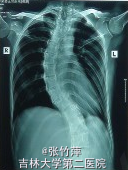

查体:患者明显外形异常。四肢细长,蜘蛛指,双臂平伸指距大于身长,双手下垂过膝,下半身比上半身长。长头畸形、面窄、高腭弓、耳大且低位。皮下脂肪少,肌肉不发达,肌张力低,呈无力型体质。脊柱侧凸。 辅查: 胸片如图一,示脊柱侧突 手部X片如图二,示蜘蛛指 手部外形如图三 右眼视力为 0.25,左眼为 0.05,双眼眼压正常;瞳孔散大后裂隙灯检查发现双眼晶状体脱位入玻璃体腔,眼底检查发现存在视网膜变性,但是未见视网膜撕裂及视网膜脱离的任何迹象。